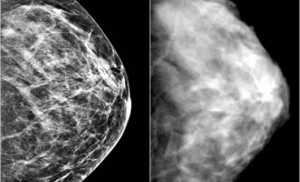

Специалисты Гарвардского университета разрабатывают новый способ лечения одного из самых распространенных видов рака у женщин.